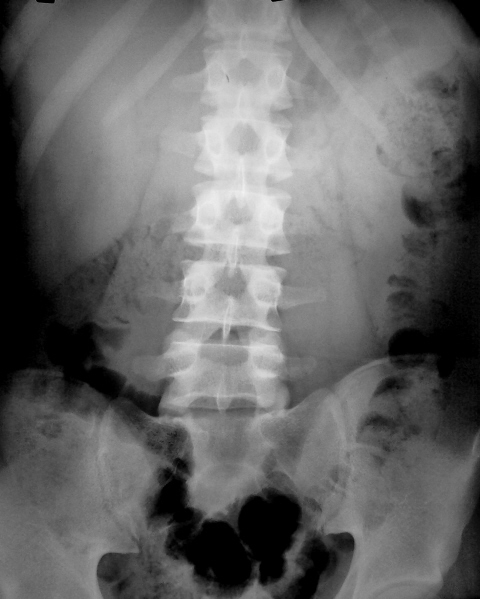

Молодой человек, 21 год.Гематурия, неясные боли в поясничной области.При УЗИ-конкремент в средней группе чашечек слева.

ИМХО: Признаков наличия конкрементов и  ретенции в коллеторных системах почек, а так же патологии со стороны мочеточников и мочевого пузыря,  на момент проведения экскреторной урографии не определяется.

По методическим дефектам: отсутствие подготовки, даже на момент проведения обзорного снимка- масса газов в толстой кишке.

По обзорной рентгенограмме почек и мочевыводящих путей, вроде придраться не к чему.

На следующем снимке, справа, и чашечно-лоханочная система, и правый мочеточник, на мой взгляд, без особого криминала.

Но, вот слева? По всей видимости, необходимо согласиться с коллегой lupan, по поводу «недостаточно тугого» контрастирования нижней группы чашечек. Что это конкременты? По всей видмости, с большей степенью вероятности можно допустить наличие чего-то «мягкотканого» - сгустки, воспалительный процесс, возможно, и стелюшийся опухолевый рост. Но, в данном конкретном случае, по всей видимости, мы натыкаемся на естественные пределы – возможности внутривенной урографии.